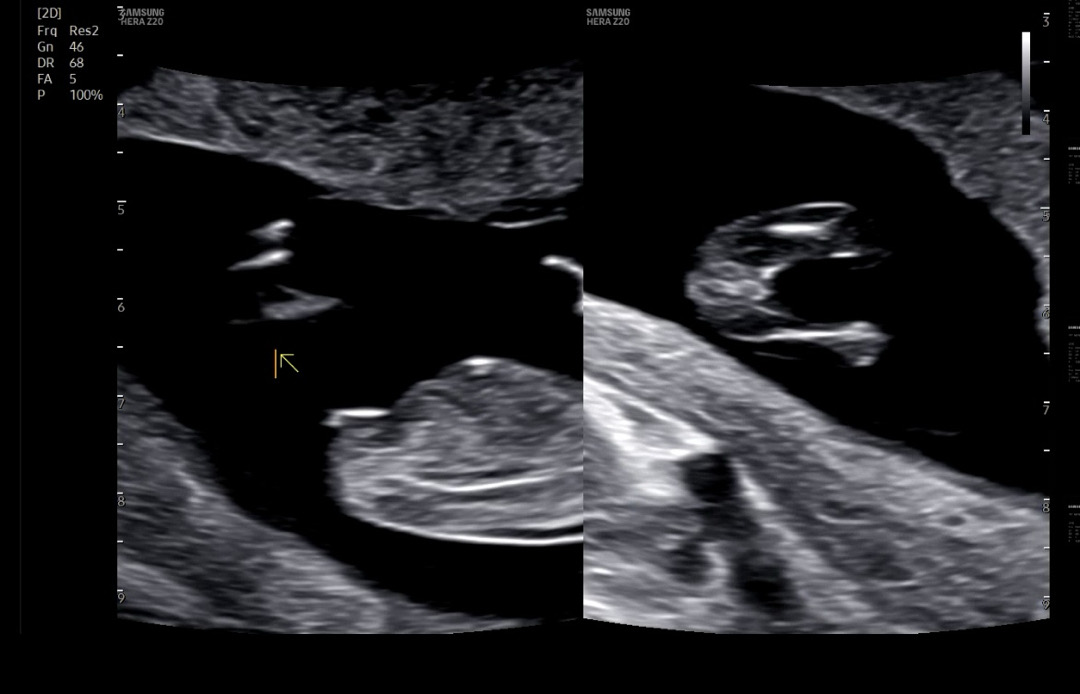

12주 2일 각도법 봐주세요🫶🏻

12주2일 오늘 1차기형아검사 하고왔어요😍 각도법 봐주세요~~🫶🏻